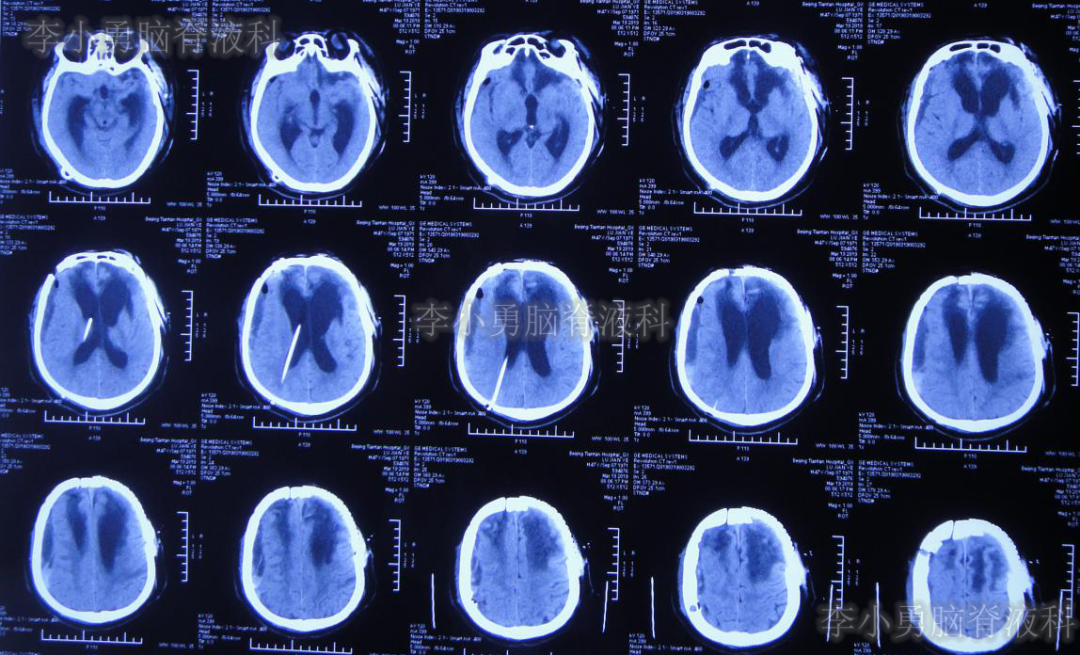

2019年3月12日即开颅术后71天,从山西太原转至北京某三甲医院;住院时复查头颅CT(图-2)示双侧侧脑室扩张,右侧硬膜下积液并少量出血,减压窗处脑膜脑膨出。

图-2:2019年3月12日头颅CT

入院1周后即2019年03月19日即开颅术后78天,进行了左侧额部颅骨缺损钛板修补术+脑室腹腔分流术。术后当天复查头颅CT(图-3)示右侧脑室内可见分流管,左侧颅骨修补术后改变,但右侧仍有硬膜下积液合并出血。

图-3:2019年3月19日头颅CT

颅骨修补及脑室腹腔分流术后1周即2019年3月27日即开颅术后86天,从第2家医院直接转回第1次开颅手术的山西省某三甲医院康复科,行康复治疗;但入院当天即出现高热39.2℃,以及恶心、呕吐症状。行胸部CT,抽血化验等检查及头颅CT(图-4)后,认为均无明显异常。

图-4:2019年3月27日头颅CT

在山西三甲医院治疗13天后,于2019年4月9日即颅骨修补术+脑室-腹腔分流术后21天,再次转回北京某三甲医院。入院当天复查头颅CT(图-5)示脑室引流术后状态。

图-5:2019年4月9日头颅CT